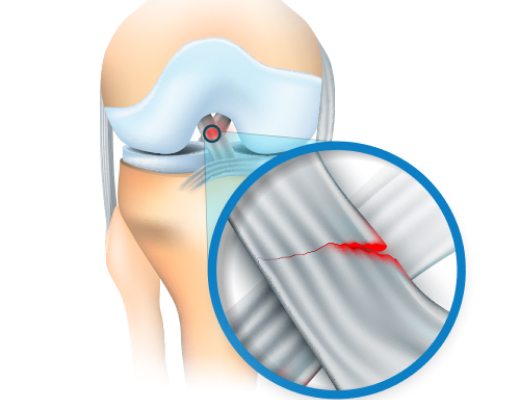

반월상 연골이란 무릎 관절 내부에서 체중분산 및 관절 연골 보호 관절내 윤활 기능을 하는 구조물로 반월상 연골판은 퇴행 변화 및 과격한 운동으로 손상을 입게 되며 피가 통하지 않는 부위라 스스로 치유가 매우 어렵고 추가적인 파열이 진행되게 됩니다.

X-ray 검사의 경우 반월상 연골을 관찰이 힘들지만 MRI 검사의 경우 무릎 안에 반월상 연골의 정확한 진단이 가능합니다.

파열된 연골

수술후